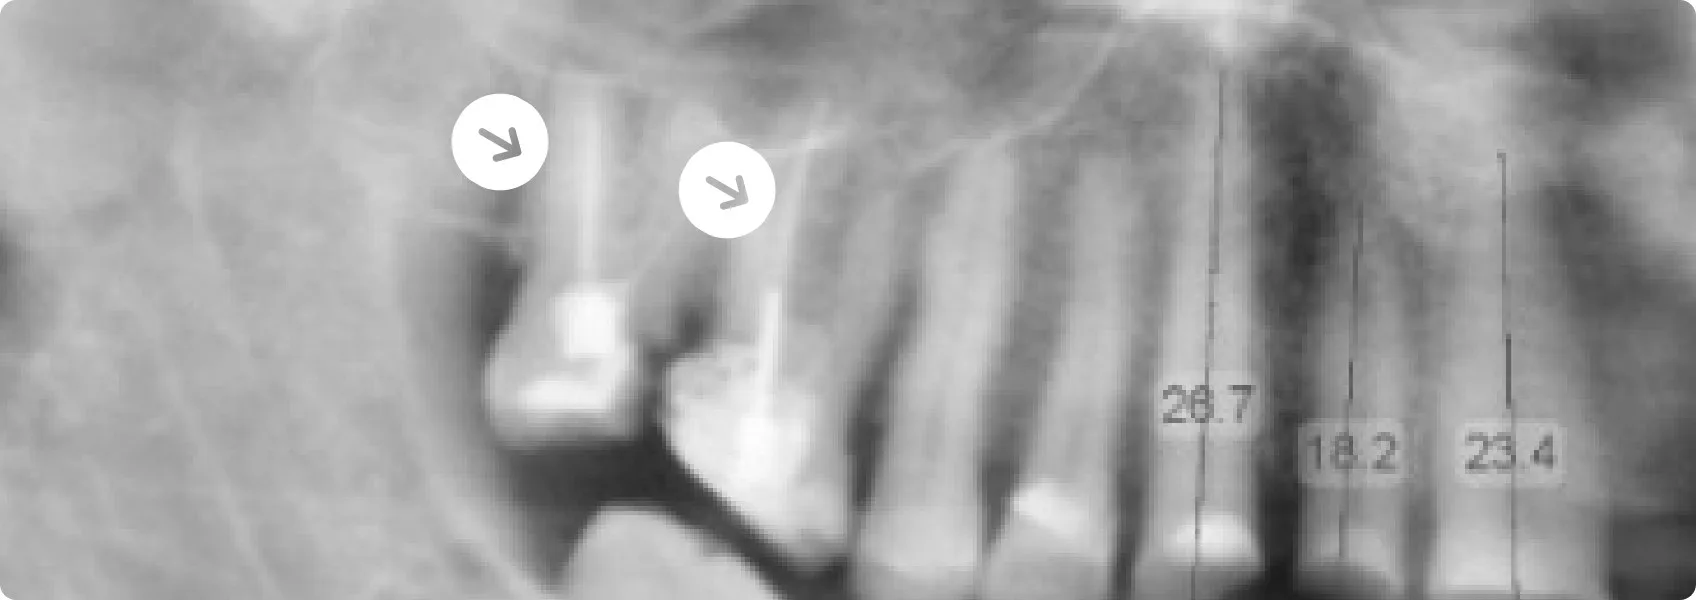

Podczas analizy zdjęć RTG stało się jasne, że jeden z zębów Pacjenta musi zostać usunięty. Ściana zęba była zbyt cienka, a zniszczenie sięgało poziomu kości.

Cienka ściana oznacza, że pozostało bardzo mało zdrowej tkanki zęba, która mogłaby wytrzymać siły działające podczas żucia. Taki ząb jest ekstremalnie podatny na pęknięcie lub całkowite złamanie, często w sposób uniemożliwiający jakąkolwiek dalszą odbudowę.

Utrzymanie go wiązałoby się ze zbyt dużym ryzykiem powikłań i awarii pracy. Podjęliśmy trudną, ale konieczną decyzję o ekstrakcji.

Diagnostyka RTG ujawniła kolejny problem. Przy korzeniach zębów, które Pacjent leczył wcześniej kanałowo w innym gabinecie, znaleźliśmy stany zapalne.

Był to sygnał, że wewnątrz tych zębów organizm walczy z infekcją, która nawróciła po pierwotnym leczeniu kanałowym